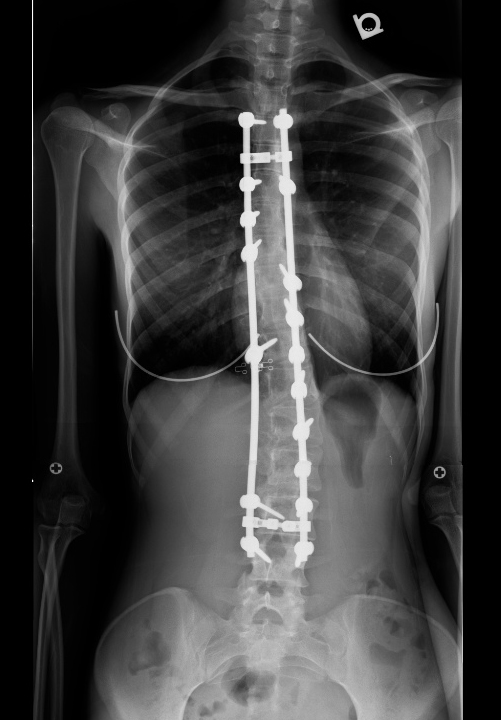

| Pre-op | Post-op |